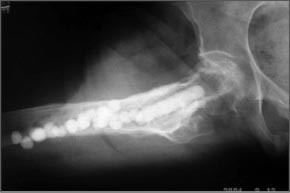

Здесь пример лечения антибиотическими бусами и форма для бус!

В нашем примере удаление пластины было произведено из-за поздней инфекции на фоне сросшегося перелома. На месте винта в шейке образовался огромный костный дефект и для профилактики стрессового перелома установили “колбаску” из остатка цемента с антбиотиком. Следующую операцию закончили замещением костного дефекта пластикой из губчатой аллокости, которая была забита в дефект.